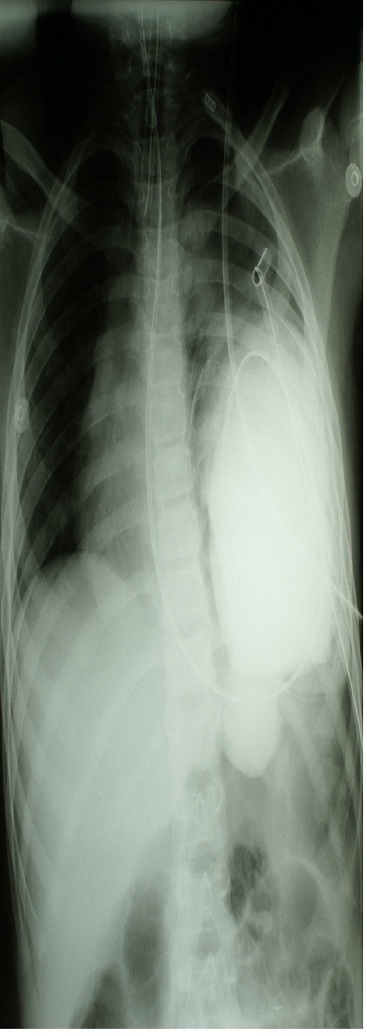

Pytanie 41

Dziewięcioletnia dziewczynka w wyniku potrącenia przez samochód osobowy doznała urazu wielonarządowego dotyczącego głowy (bez objawów krwawienia śródczaszkowego), klatki piersiowej i brzucha oraz lewego podudzia. Nieprzytomną dziewczynkę zaintubowano. Zdjęcie przeglądowe klatki piersiowej i brzucha wykazało trudny do zinterpretowania obraz. Zdecydowano wykonać badanie radiologiczne z podaniem przez sondę kontrastu do żołądka. Uzyskano następujący wynik:

Zaproponuj optymalne postępowanie chirurgiczne: